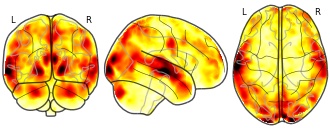

EmailClick to copy linkLink copied Cite(2019). Brain activity during reciprocal social interaction investigated using conversational robots as control condition: Contrast human-robot interaction (HRI) versus human-human interaction (HHI) [Dataset]. http://identifiers.org/neurovault.image:112530niftiAvailable download formatsUnique identifierhttps://identifiers.org/neurovault.image:112530Dataset updatedMar 19, 2019License

Cite(2019). Brain activity during reciprocal social interaction investigated using conversational robots as control condition: Contrast human-robot interaction (HRI) versus human-human interaction (HHI) [Dataset]. http://identifiers.org/neurovault.image:112530niftiAvailable download formatsUnique identifierhttps://identifiers.org/neurovault.image:112530Dataset updatedMar 19, 2019LicenseCC0 1.0 Universal Public Domain Dedicationhttps://creativecommons.org/publicdomain/zero/1.0/

License information was derived automaticallyDescriptionContrast human-robot interaction (HRI) versus human-human interaction (HHI)

We present a novel paradigm for social neuroscience comparing a human social interaction (human-human interaction, HHI) to an interaction with a conversational robot (human-robot interaction, HRI) during functional magnetic resonance imaging (fMRI). We recorded 1-minute blocks of live bidirectional discussion between a participant in scanner and another human (confederate) or a robot agent outside the scanner. A cover story provides the topic of the discussion while hiding to participants the true objectives of the experiment. To this end, we collected multimodal data including fMRI data, behaviour (speech from the participant and human or robot agent, video capture of the human and robot agent, and the gaze movement of the scanned participant) and physiology (BOLD signal, respiration and peripheral blood flow pulse) to form a corpus.

Experimental paradigm

The MRI recordings consisted of four sessions of each six 1-minute blocks of conversation each, showing anthropomorphized fruits and vegetables as “super-heroes” images in the first and third sessions and images of anthropomorphized “rotten fruits” images in the second and fourth sessions. The order was kept constant across participants each session alternating the three images per session and two interacting agents and starting with the human agent (ie Image1/Human, Image2/Robot, Image3/Human, Image1/Robot, Image2/Human, Image3/Robot). Each image was thus shown twice in each session, once per interacting agent.

Blocks started with the presentation of one image for 8.3 seconds, followed by a 3.3 second black screen, after which there was a live bidirectional conversation with the interacting agent for one minute, followed by an inter block interval black screen of 4.6 seconds. In the absence of live video feed from inside the scanner, a light signaled to the confederate that the conversation had started. The participant initiated the conversation, instructed to talk freely with the other agent about the image and their suggestions on the topic of the advertisement campaign. One block lasted 76.2 seconds and one session 8 minutes and 2 seconds of fMRI recording. We recorded 3 minutes of conversation per interacting agent and session, for a total of 24 minutes of conversation per participant. Audio and video set-up of the conversation was tested beforehand, and audio adjusted individually for each participant. As participants were always connected via audio with the confederate, they mentioned if they couldn’t hear well, giving us the chance to adapt the audio if required. This information was recorded for future use.MRI acquisition

MRI data was collected with a 3T Siemens Prisma (Siemens Medical, Erlangen, Germany) using a 20-channel head coil. Blood oxygen level-dependent (BOLD) sensitive functional images were acquired using an EPI sequence in the 4 runs. Parameters were as follows: Echo time (TE) 30 ms, repetition time (TR) 1205 ms, flip angle 65°, 54 axial slices co-planar to the anterior / posterior commissure plane, FOV 210mm x 210mm, matrix seize 84 x 84, voxel size 2.5 x 2.5 x 2.5 mm3, with multiband acquisition factor 3. After functional scanning, structural images were acquired with a GR_IR sequence (TE/TR 0.00228/2.4 ms, 320 sagittal slices, voxel size 0.8 x 0.8 x 0.8 mm, field of view 204,8 x 256 x 256mm).MRI data analysis

MRI data was analysed using SPM12 (Statistical Parametric Mapping, http://www.fil.ion.ucl.ac.uk/spm/). First, we calculated the voxel displacement map. The time series for each voxel was then realigned temporally to the acquisition of the slice in the middle in time to correct for differences in slice time acquisition. The image time series were unwarped using the voxel-displacement map to take into account local distortion of the magnetic field and spatially realigned using a sinc interpolation algorithm that estimates rigid body transformations (translations, rotations). Images were then spatially smoothed using an isotropic 5 mm full-width-at-half-maximum Gaussian kernel. The first realigned and unwarped functional image was coregistered with an unwarped single-band-reference image recorded at the onset of each trial, which was itself coregistered with the T1 and T2 anatomical images. These anatomical images were segmented into grey matter (GM), white matter (WM), and cerebral spinal fluid (CSF) using SPM12 “New segment”. GM, WM, and CSF tissue probability maps were used to form a DARTEL template (Ashburner, 2007). The deformation flow fields from individual spaces to this template were used to normalize the beta images resulting from the individual subjects’ analyses (i.e. in subjects’ individual space) for use in a random-effect second-level analysis.

Potential artefacts from blood pulse and respiration were controlled using the Translational Algorithms for Psychiatry-Advancing Science (TAPAS) toolbox standard procedure (https://www.tnu.ethz.ch/de/software/tapas/documentations/physio-toolbox.html; Kasper et al., 2017). Realignment parameters (translation and rotation) as well as their derivatives and the square product of both parameters and their derivatives were used as covariates to control for movement-related artefacts. We also used the Artefact Detection Tools (ART) to control for any movement-related artefacts (www.nitrc.org/projects/artifact_detect/) using the standard threshold of 2 mm.

The fMRI time series were analysed using the General Linear Model (GLM) approach implemented in SPM. Single-subject models consisted of one regressor representing the one-minute discussion for each of the two interacting agents, and another one representing the presentation of the images.

After normalization, beta estimates images were entered in a mixed-model analysis of variance (using SPM “full ANOVA”) with participants and sessions as random factors and the nature of the interacting agent as factor of interest for inferences at the population level. A mask was created on the basis of the mean of DARTEL normalized anatomical GM and WM tissue classes of each participant, also used for rendering results in Figure 3.

We first assessed the main effect of the conversation with both agents against the implicit baseline. We then looked specifically at the effects of each of the interacting agent contrasted to the other one, with a clear focus on brain areas involved in mentalizing and social motivation in the contrast HHI versus HRI.

All statistical inference was performed applying a threshold of p = 0.05 False-Discovery Rate (FDR) corrected for the whole brain at the cluster-level (Friston, Holmes, Poline, Price, & Frith, 1996). Anatomical localization of the resulting clusters relied on the projection of the results onto the mean anatomical image of our pool participants resulting from DARTEL coregistration.Description partly taken from Rauchbauer, B. et (2016; pp 8 - 10), under revision